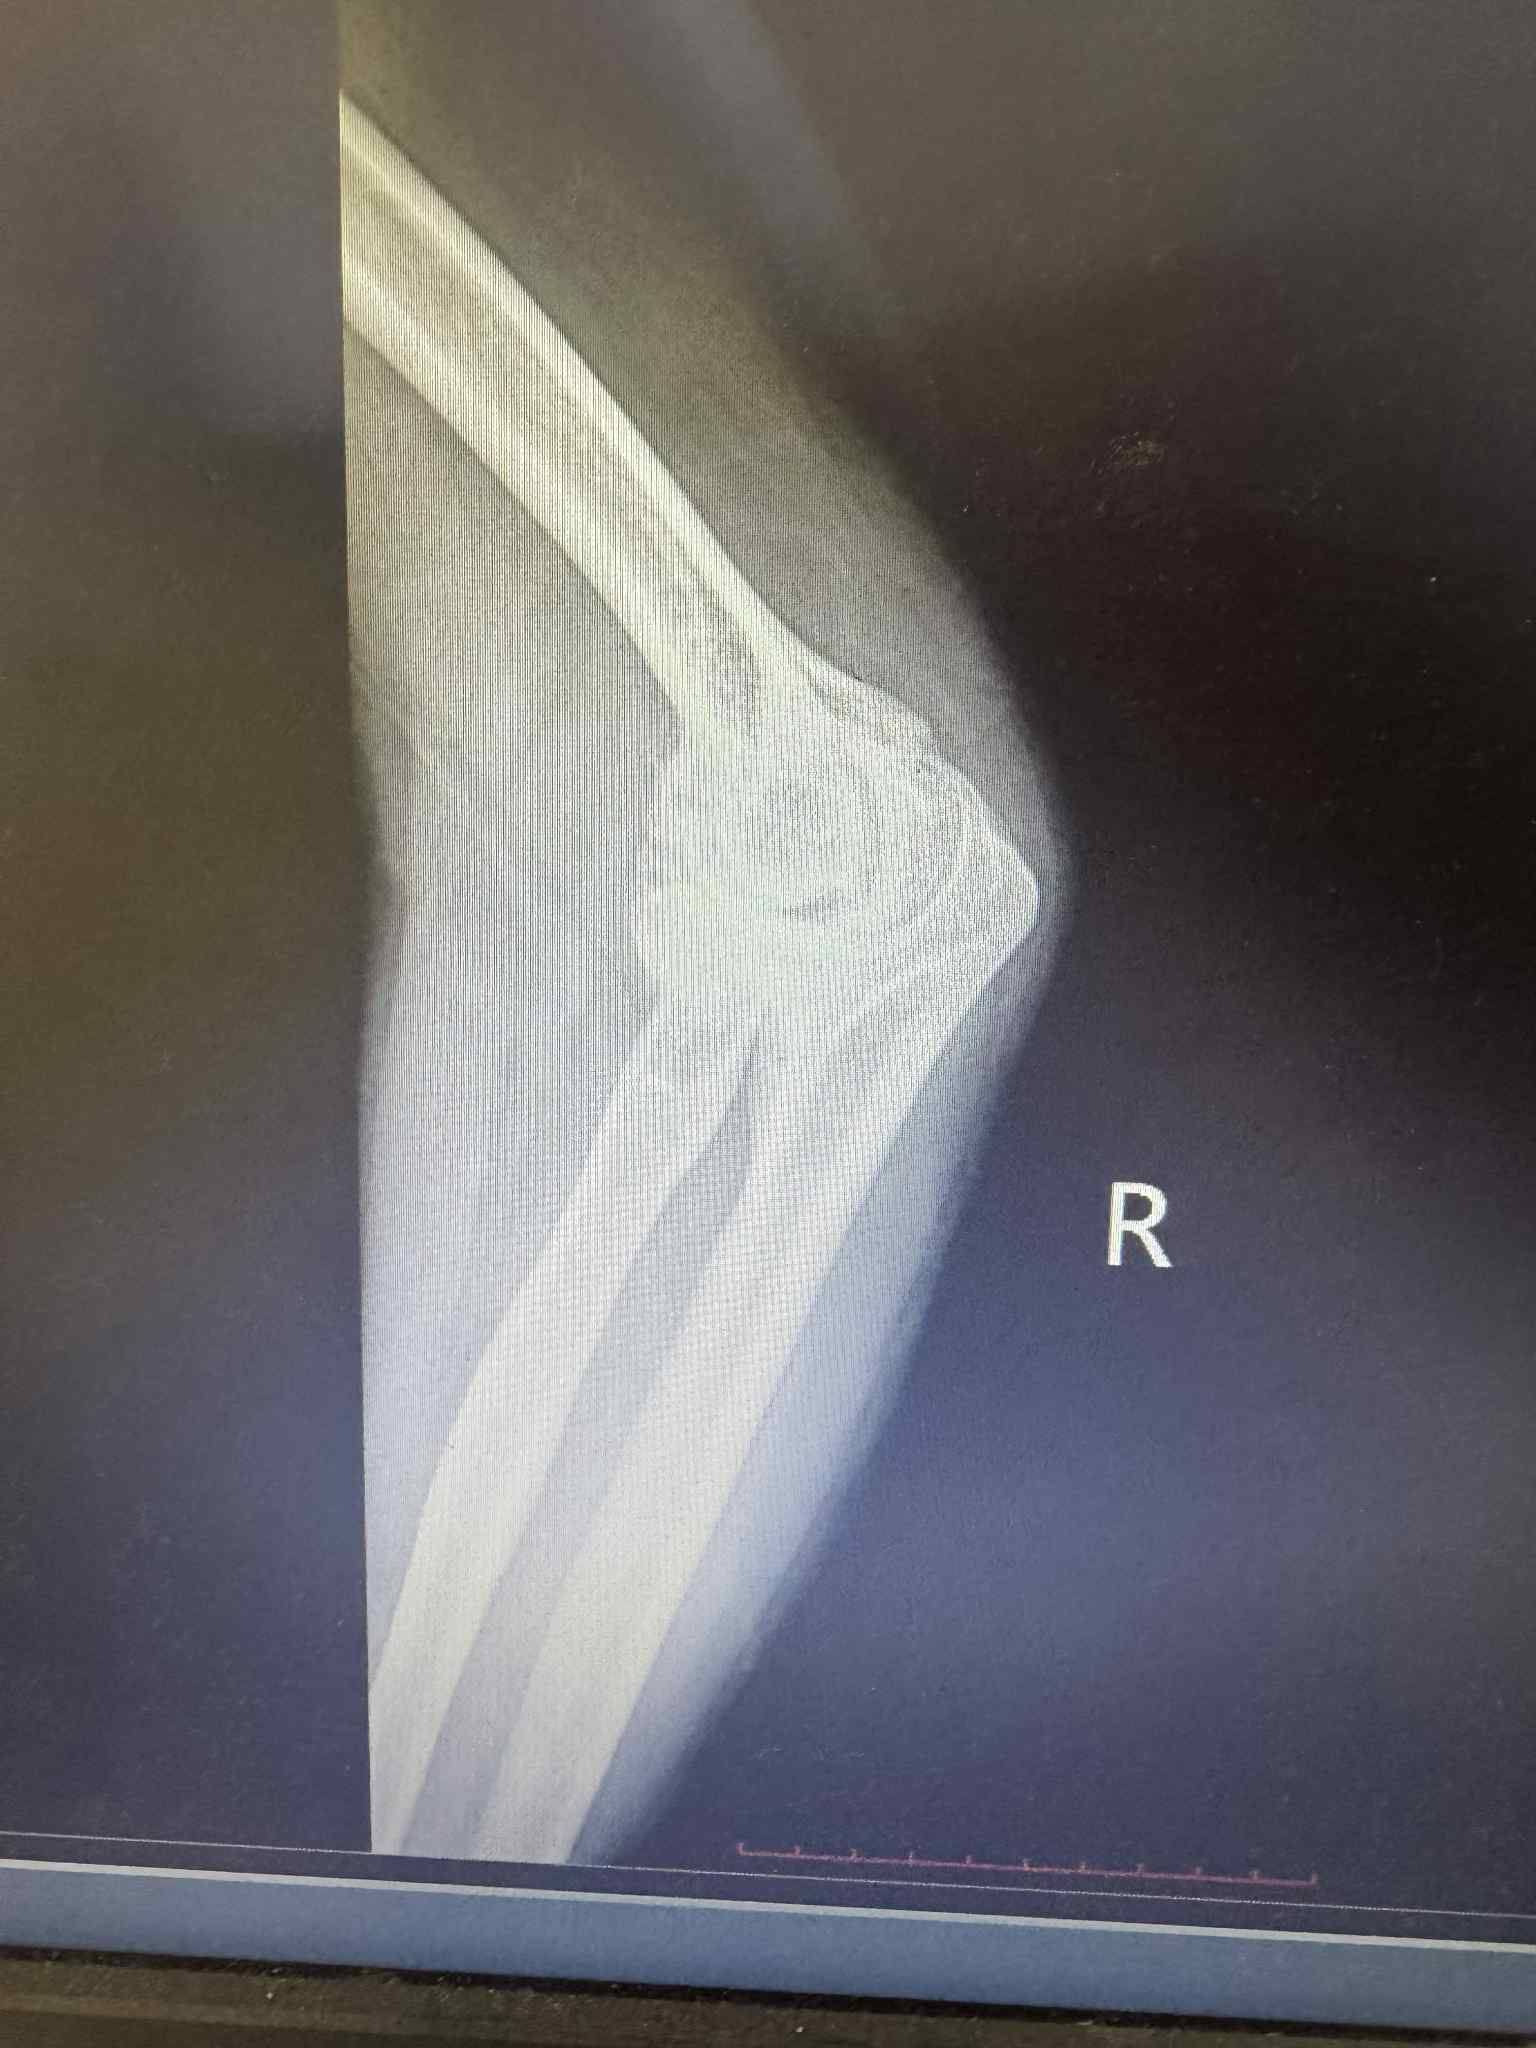

Төв аймгийн Нэгдсэн эмнэлгийн мэс заслын тасгийн гэмтлийн эмч нар Гэмтэл согог судлалын үндэсний төвийн эмч нартай хамтран орон нутагтаа анх удаа тохойн үе бүтэн солих мэс заслыг амжилттай нэвтрүүллээ.